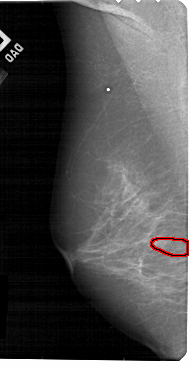

A_1839_1.RIGHT_CC

RIGHT_CC LINES 5221 PIXELS_PER_LINE 2281 BITS_PER_PIXEL 12 RESOLUTION 43.5 NON_OVERLAY

FILE: A_1839_1.LEFT_CC.OVERLAY

TOTAL_ABNORMALITIES 1

ABNORMALITY 1

LESION_TYPE CALCIFICATION TYPE PLEOMORPHIC DISTRIBUTION CLUSTERED

ASSESSMENT 4

SUBTLETY 3

PATHOLOGY BENIGN

TOTAL_OUTLINES 1

BOUNDARY